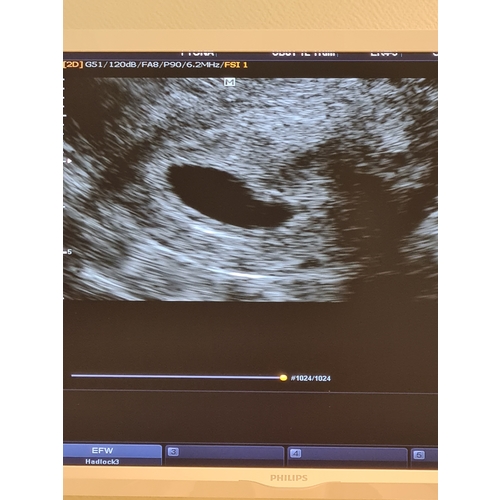

Kans Op Leeg Vruchtzakje . Kans op Zwangerschap Feiten, Vruchtbaarheid en Tips Bij mij was er een leeg vruchtzakje te zien met ongeveer 5+5 het is nog veel te vroeg om daar een uitspraak over te doen Medisch gezien heeft het de voorkeur om enige tijd af te wachten totdat de miskraam spontaan optreedt

Source: cohlarslse.pages.dev 4 weken en leeg vruchtzakje 1 24baby Forum , Bij mij was er een leeg vruchtzakje te zien met ongeveer 5+5 het is nog veel te vroeg om daar een uitspraak over te doen Een lege vruchtzak of een niet-levend embryo zonder hartactie zijn bij deze zwangerschapsduur met echoscopie.

Source: biolatrvn.pages.dev Wat is de kans? , De echo wijst uit dat het hartje niet meer klopt of dat het vruchtzakje leeg is Helaas was er op de echo alleen een leeg vruchtzakje te zien